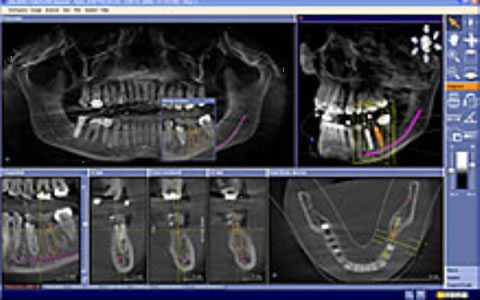

当院が導入しております最新の歯科用CT「SL」を使用することで、どの角度からでも口腔内の歯、骨格、神経など歯科治療に必要な情報を確認することが出来ます。また、従来のCTではデータ解析をするのに多大な時間を要し、診断可能になるまで14日以上ものロスがありましたが、このCTは撮影して数分後に口腔内を確認することが可能となっております。

インプラント治療計画ソフトウェア 複雑な治療計画をサポート

CGのインプラントソフトウェアは、神経管や骨格がビジュアル化され確認しやすく解剖学的な私見を必要とする患者様のインプラント治療に適したソフトウェアです。より正確なプランニングと埋入により安全性の確保を促し、不要なストレスが低減されます。治療状態を確認しインプラント埋入本数を増やすだけではなく、患者様へのプレゼンテーションにおいても3D画像により患者様への説明をサポートします。

インプラント設計診断分析

正確な診断の為の正確無比なCT撮影